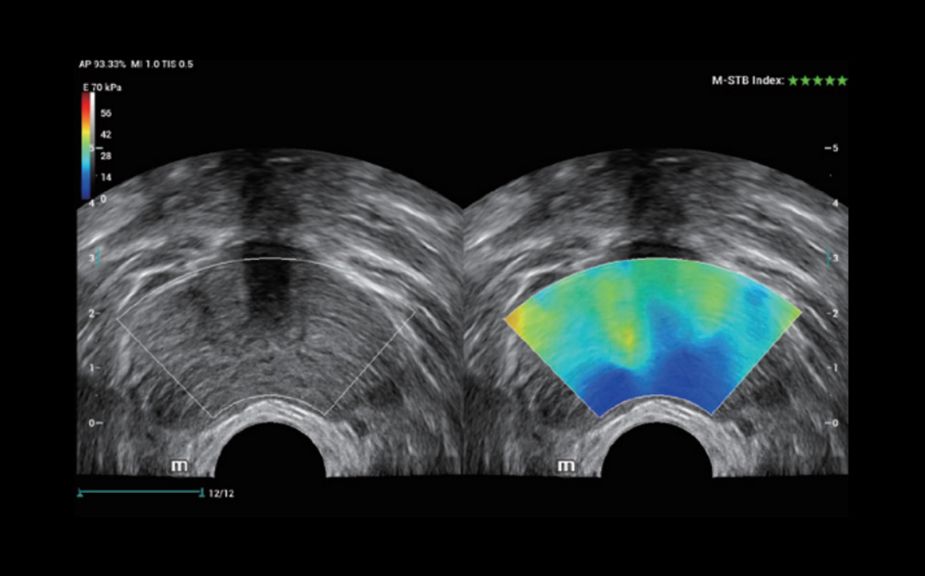

Инновационная оценка жесткости: HiFR STE

В 10 раз более высокая частота кадров при работе режима STE

Высокая чувствительность к движению для повышения стабильности и точности

HiFR STE новообразования молочной железы

HiFR STE печени

Инновационная оценка жесткости: HiFR STE

В 10 раз более высокая частота кадров при работе режима STE

Высокая чувствительность к движению для повышения стабильности и точности

HiFR STE новообразования молочной железы

HiFR STE печени